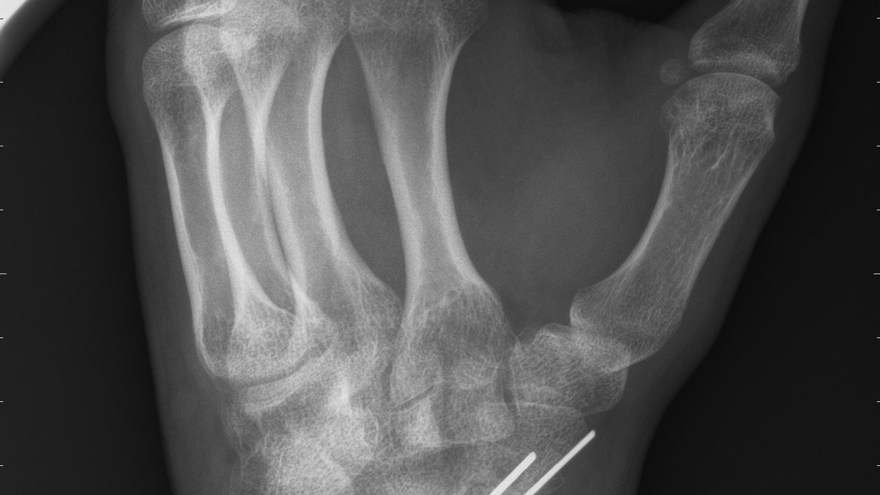

Subcapitulär metacarpalfraktur

Subcapitulär metacarpalfraktur är en vanlig slagsmålsskada och drabbar då ofta metacarpale V. Frakturen dislocerar alltid volart och viss kvarvarande volarställning (ca 30-40° i MCP V) kan accepteras. Behandlas annars med sluten reposition och gips i 3 veckor.